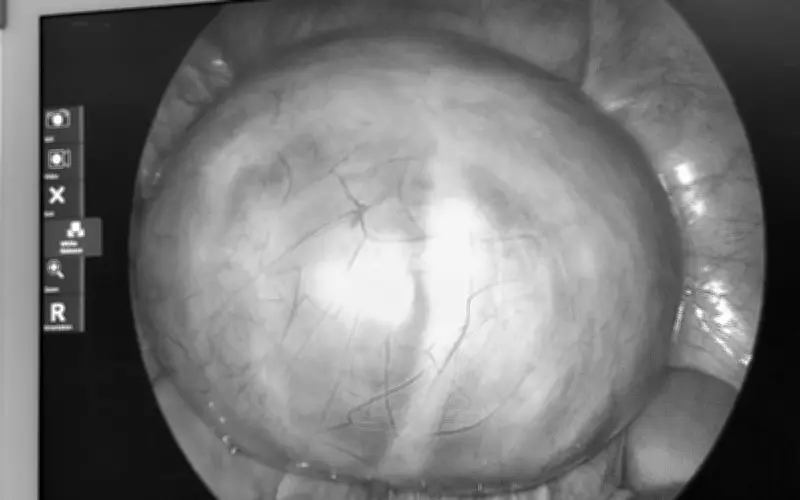

Theo thông tin ban đầu, bệnh nhân V.T.T.V. trước đó không thực hiện khám phụ khoa định kỳ do không có triệu chứng rõ ràng nào. Đến ngày 31/3, khi xuất hiện tình trạng đau tức bụng, chị mới quyết định đến bệnh viện để thăm khám. Ban đầu, chị chỉ nghĩ đây là cơn đau bụng thông thường, nhưng kết quả siêu âm đã khiến mọi người bất ngờ khi phát hiện một khối u lớn khoảng 14cm ở buồng trứng trái, với cấu trúc nhiều vách phức tạp.

Sau khi hội chẩn kỹ lưỡng, ê-kíp khoa Phụ sản của bệnh viện đã tiến hành phẫu thuật vào ngày 3/4. Ca mổ diễn ra thuận lợi, khối u được bóc tách hoàn toàn mà vẫn bảo tồn tối đa chức năng sinh sản cho người bệnh. ThS.BS. Bùi Thị Viễn Phương, Phó Trưởng khoa Phụ sản, cho biết u nang buồng trứng là bệnh lý khá phổ biến ở phụ nữ, nhưng thường diễn tiến âm thầm và ít biểu hiện ở giai đoạn đầu.